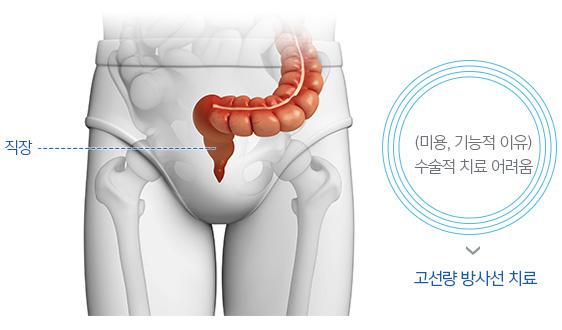

직장암의 양성자치료에 대한 자세한 정보를 소개합니다

수술이 쉽지 않은 재발 직장암에서 수술 전후 고선량 방사선치료를 위해 적용될 수 있습니다.

이미 방사선치료를 시행한 적 있는 재발 직장암의 경우 우선 고려될 수 있습니다.

기능적, 미용적 이유로 수술적 치료가 제한적이고,

고선량 방사선치료가 시행되지만, 총 방사선 전달량에 제한이 있어,

이미 방사선치료가 시행된 재발 직장암의 경우 종양 제거가 어렵고, 수술의 경우 미용적, 기능적 제한이 큰 것으로 알려져 있습니다. 따라서 고선량의 방사선 재 치료가 시행되는 경우가 많은데, 이 경우 세기조절 방사선치료를 시행하더라도 주변 정상 장기에 노출되는 방사선으로 인한 부작용이 흔하며, 총 방사선량이 제한되어 5년 종양 제어율이 50% 이하로 알려져 있습니다. 하지만 주변 정상 장기에 방사선 노출을 크게 낮출 수 있는 양성자치료는 부작용에 대한 우려를 낮추면서 고선량의 방사선을 전달하여 종양을 제거할 수 있을 것으로 기대하고 있습니다.